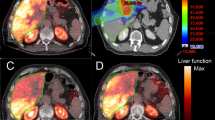

90Y PET dosimetry was calculated using a commercial image analysis software (Imalytics, Philips Technologie GmbH, Innovative Technologies, Aachen, Germany) on a 3D workstation. Volumes of interest corresponding to the anatomic margins of the treated tumors and surrounding non-tumoral liver lobe (entire right or left liver lobar volume, ipsilateral to the treated arterial distribution, excluding the tumors) were selected (Fig. 1) using the pre-treatment multiphase CT or MR by a single board-certified radiologist with 1 year of experience who was blinded to the primary outcome and the 90Y treatment [18]. The number of coincident events was assessed for each voxel across the volumes of interest, allowing for a 90Y dose and a dose-volume histogram to be calculated based on a pre-calibrated conversion factor. The median delivered dose and median volume of the non-tumoral liver lobe were recorded.

A 65 year old with a large partially necrotic hepatocellular carcinoma in segment 5/6. B Volumes of interest were superimposed on baseline contrast-enhanced CT delineating tumor (green) from normal liver (pink). C Lobar radioembolization was performed using glass microspheres, with post-radioembolization PET fused with baseline CT showing heterogeneous microsphere distribution within the tumor and the surrounding parenchyma. D Volumes of interest corresponding with 90Y distribution. In this case, the dose to the normal liver parenchyma was 69 Gy and the dose to the tumor was 268 Gy